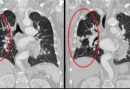

전이성 폐암

전이성 폐암 (정의)폐암은 원발성 폐암과 전이성 폐암으로 나눌 수 있는데 원발성 폐암은 폐에 발생된 암인 것에 비하여, 전이성 폐종양은 타 장기에서 발생된 악성 종양이 폐에 전이된 것을 말합니다. 그 대부분은 원격전이라고 하며 타 장기에 존재하는 종양세포가 혈류를 따라…